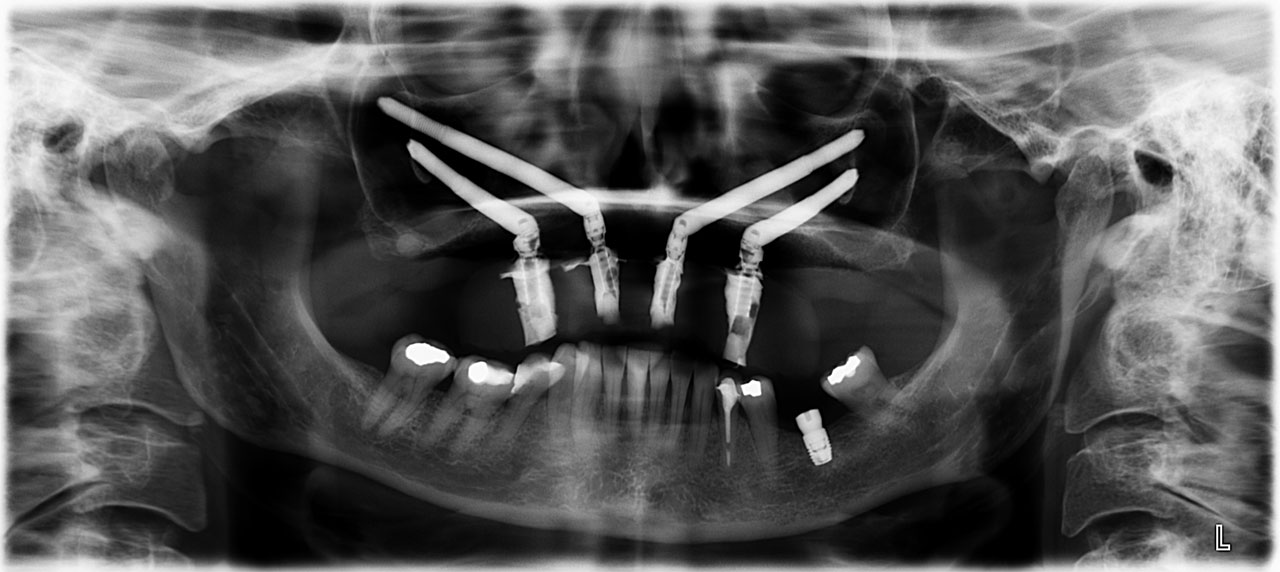

Dans les cas où les patients présentent une atrophie osseuse sévère et importante, il n’est pas possible de procéder à la mise en place d’implants conventionnels due à une quantité et une qualité osseuse insuffisantes. Pour ces patients, les implants zygomatiques représentent une solution de traitement. Les implants zygomatiques sont beaucoup plus longs que les implants conventionnels et sont placés au niveau de l’os de la joue (os zygomatique ou os malaire). Ces implants permettent l’ancrage et la stabilité pour la confection d’une prothèse fixe temporaire. La pose d’implants zygomatiques est planifiée par ordinateur à l’aide d’un logiciel qui permet de déterminer la position idéale des implants pour obtenir une meilleure intégration et une meilleure fonction. La chirurgie s’effectue sous anesthésie locale avec sédation intraveineuse ou sous anesthésie générale. La confection d’une prothèse complète fixe temporaire peut être effectuée la journée même ou le lendemain de la chirurgie (dans la plupart des cas).

Implant zygomatique

radiologie